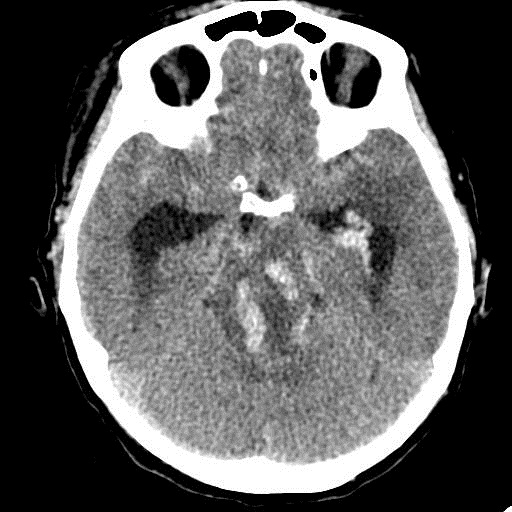

Острое внутримозговое кровоизлияние с выходом крови в желудочки (боковые - сгустки преимущественно в левом + эффект седиментации с горизонтальным уровнем жидкость\жидкость в задних рогах; сгустки крови в третьем желудочке, кровь в четвертом). Значительное увеличение височных рогов боковых желудочков - гидроцефалия. Смешение срединных структур вправо, отек белого вещества перивентрикулярно слева.

Довольно большие кровоизлияния в стволе мозга (что объясняет тяжесть состояния).

У, сколько всего написано. Пока не пришла Nela, поучаствую и я. 1. Кровоизлияние в ткань мозга, а не в опухоль: а)не видно ткани опухоли; б) неясна первичная локализация опухоли (левые базальные ядра?!); в)нет перифокального отека вокруг предролагаемой опухоли, г) при опухолях прорывы в желудочки - редкость; 2) к поперечной дислокации добавил бы безесловную аксиальную: даже цистерна моста сужена, не говоря уже про обходную-четверохолмную и другие; 3) менингиома в левой лобной области, на мой взгляд, сомнительна (кстати, покажите ее пожалуйста), ИМХО - "игра" плотностей;  4) ///метастазы в сосудистые сплетения/// - это очень круто, но они не дали бы внутримозгового кровоизлияния, как и ///плексуспапилома///.

PS. Не очень понял про ///отек мозга///, есть снижение плотности (отек и ишемия) белого вещества левого полушария и задних отделов правого.

Массивное медиальное кровоизлияние с прорывом в желудочки. Кровоизлияние в ствол. Признаки вклинения. В лбу может что-то и есть, но это не принципиально. А может быть и отечные извилины. Смущает, что нет масс-эффекта.

Про отек: субарахноидальных щелей совсем нет, по белому веществу и в стволе снижение плотности, извилины утолщены, серое вещество на этом фоне выглядит более светлым, толстым, подушкообразным.

Причина таких кровоизлияний, как правило, гипертензия и атеросклероз.

Кровоизлияние не связанное с объемным образованием, "гипертоническое", основной массой - в области базальных ядер, кровоизлияние в ствол мозга, кома ясного происхождения :) А менингиома менигниомой, не мешает, так сказать.  Отека мозга здесь небольшой, больше выражено набухание.